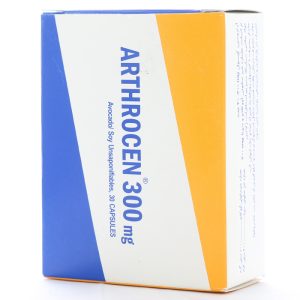

کپسول آرتروسن 300

120,000 تومان

کپسول آرتروسن، با احتوای عصارههای آووکادو و سویا، از فرآیند تخریب غضروفها جلوگیری میکند و به عنوان یکی از بهترین راهکارها برای درمان آرتروز شناخته میشود.

کپسول آرتروسن با بهبود تغذیه بافت همبند، از تخریب غضروفها پیشگیری میکند و منجر به بهبود ساختار استخوانها میشود. کپسول آرتروسن، با خاصیت ضد التهاب و بدون حاوی مواد نگهدارنده، یکی از داروهای استثنایی برای کاهش پیشرفت استئوآرتریت محسوب میشود.

علاوه بر این، مصرف کپسول آرتروسن باعث افزایش قدرت حرکت مفاصل میگردد و همچنین تخریب کلاژن را مهار و سنتز آن را تحریک میکند. جهت آشنایی بیشتر با بیماری استئوآرتریت، در ادامه با ما همراه باشید.برای تهیهي کپسول آرتروسن به داروخانه آنلاین دارونت مراجعه فرمایید.

ویژگی های کپسول آرتروسن

جلوگیری از تخریب غضروفها و درمان بافت همبند شامل استئو آرتریت

کمک به ترمیم غضروفها و ترمیم مفاصل آسیب دیده

بهبود ساختار استخوانی و پیشگیری از پوکی استخوان

تغذیه اجزاء بافت همبند و تحریک کلاژن سازی

بهبود علائم آرتروز

روزانه یک عدد کپسول آرتروسن به همراه غذا و همراه با آب فراوان میل شود.

| برند | |

| شکل دارویی |

| دسته مصرفی |

| مناسب برای |

| شرکت سازنده |

| کشور سازنده |

| تحت لیسانس |

| وب سایت مرجع |

| تعداد در جعبه |

| نوع بسته بندی |